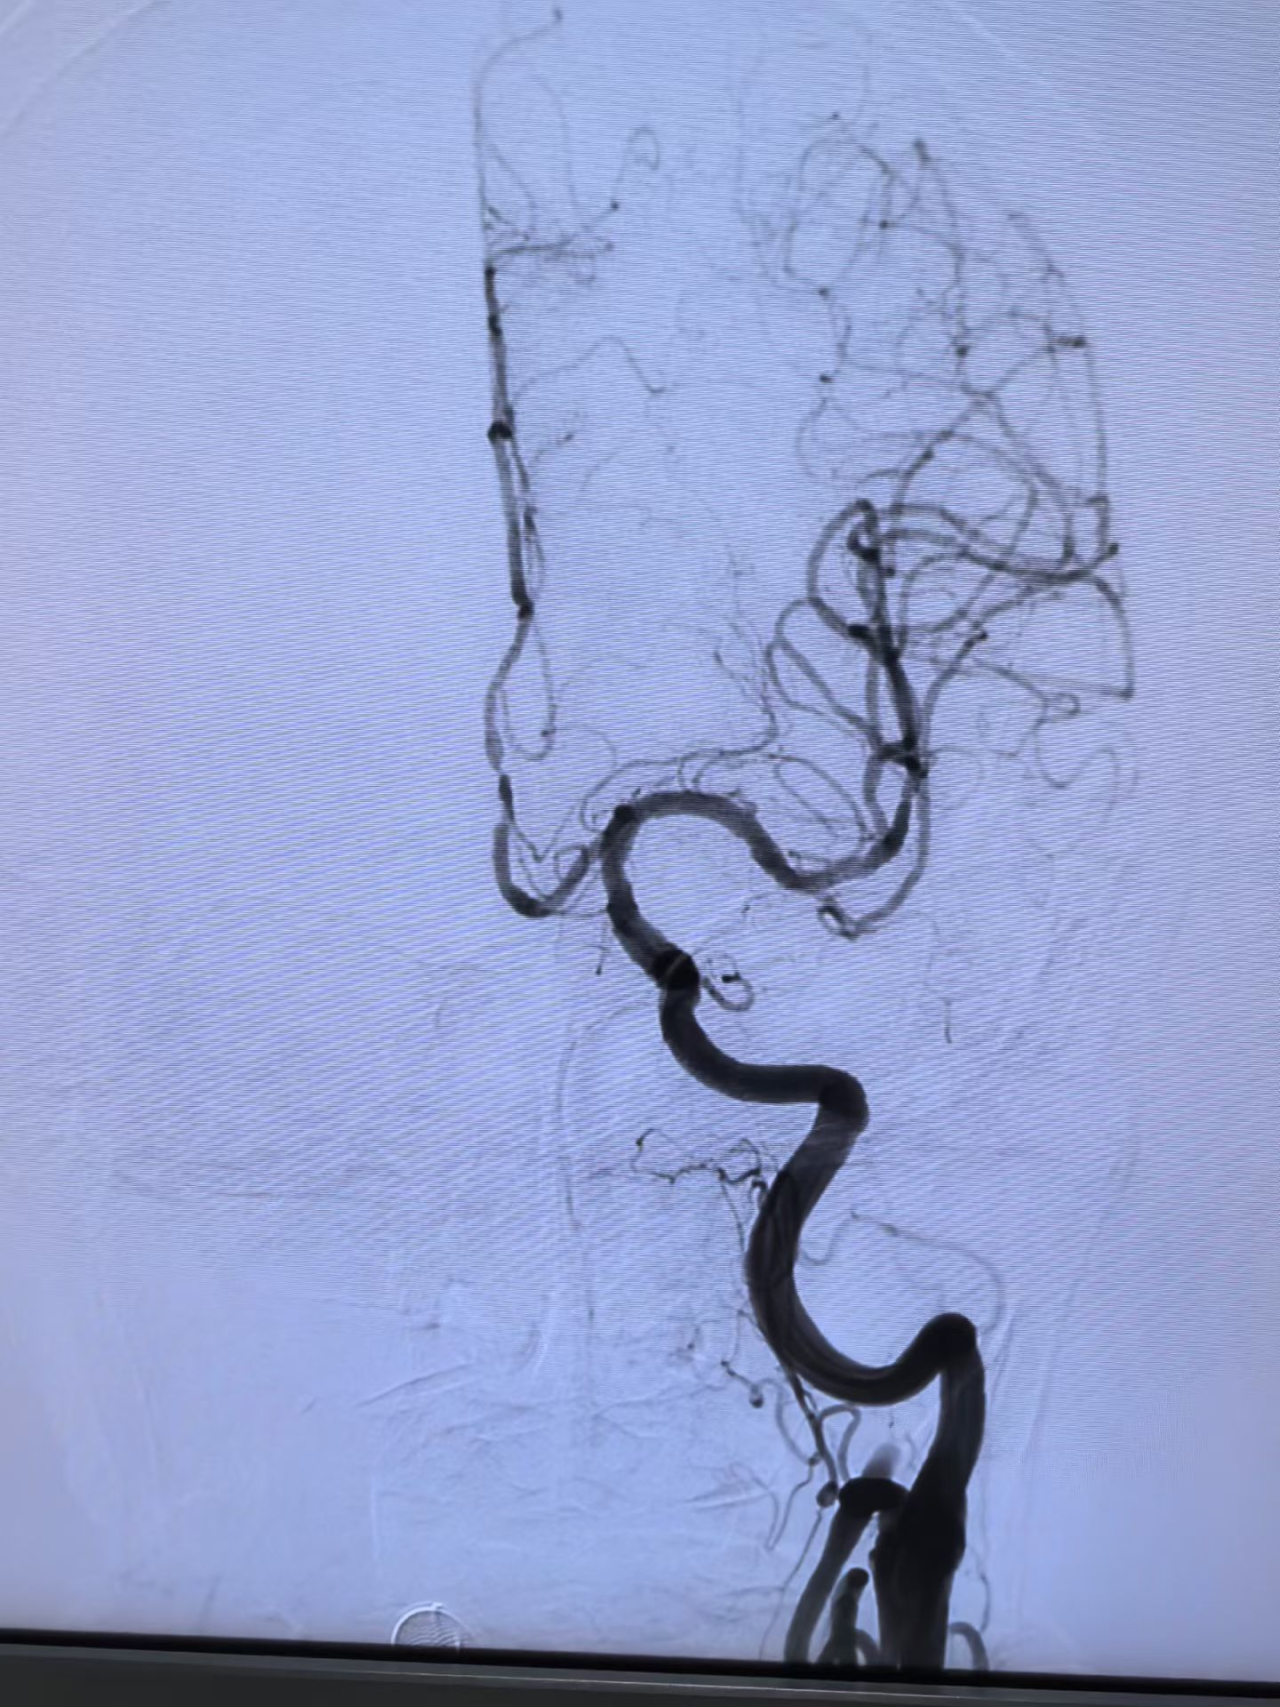

与家属充分沟通后,医疗团队决定迎难而上,为王奶奶实施了“取栓支架保护下脑动脉取栓术”,在一个小时内成功将堵塞在左侧颈内动脉及大脑中动脉的大量血栓取出,瞬间恢复了大脑供血。

急诊介入手术前后血管